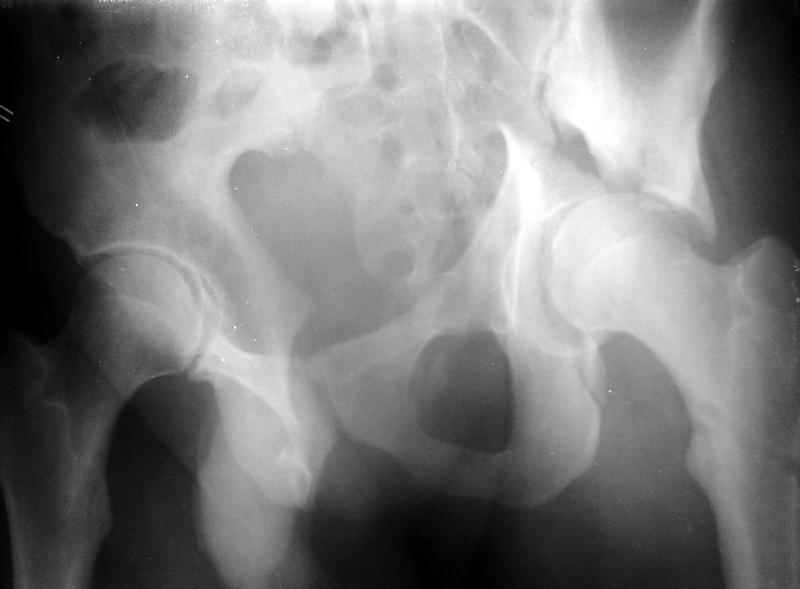

Сегодня на приеме был пациент, чьи начальный снимок напомнил обсуждаемый сейчас (см. выше). Снимки в других проекциях, показывающие истинный характер повреждения, ниже. Это inlet проекция (вход в таз) и запирательная проекция Judet.